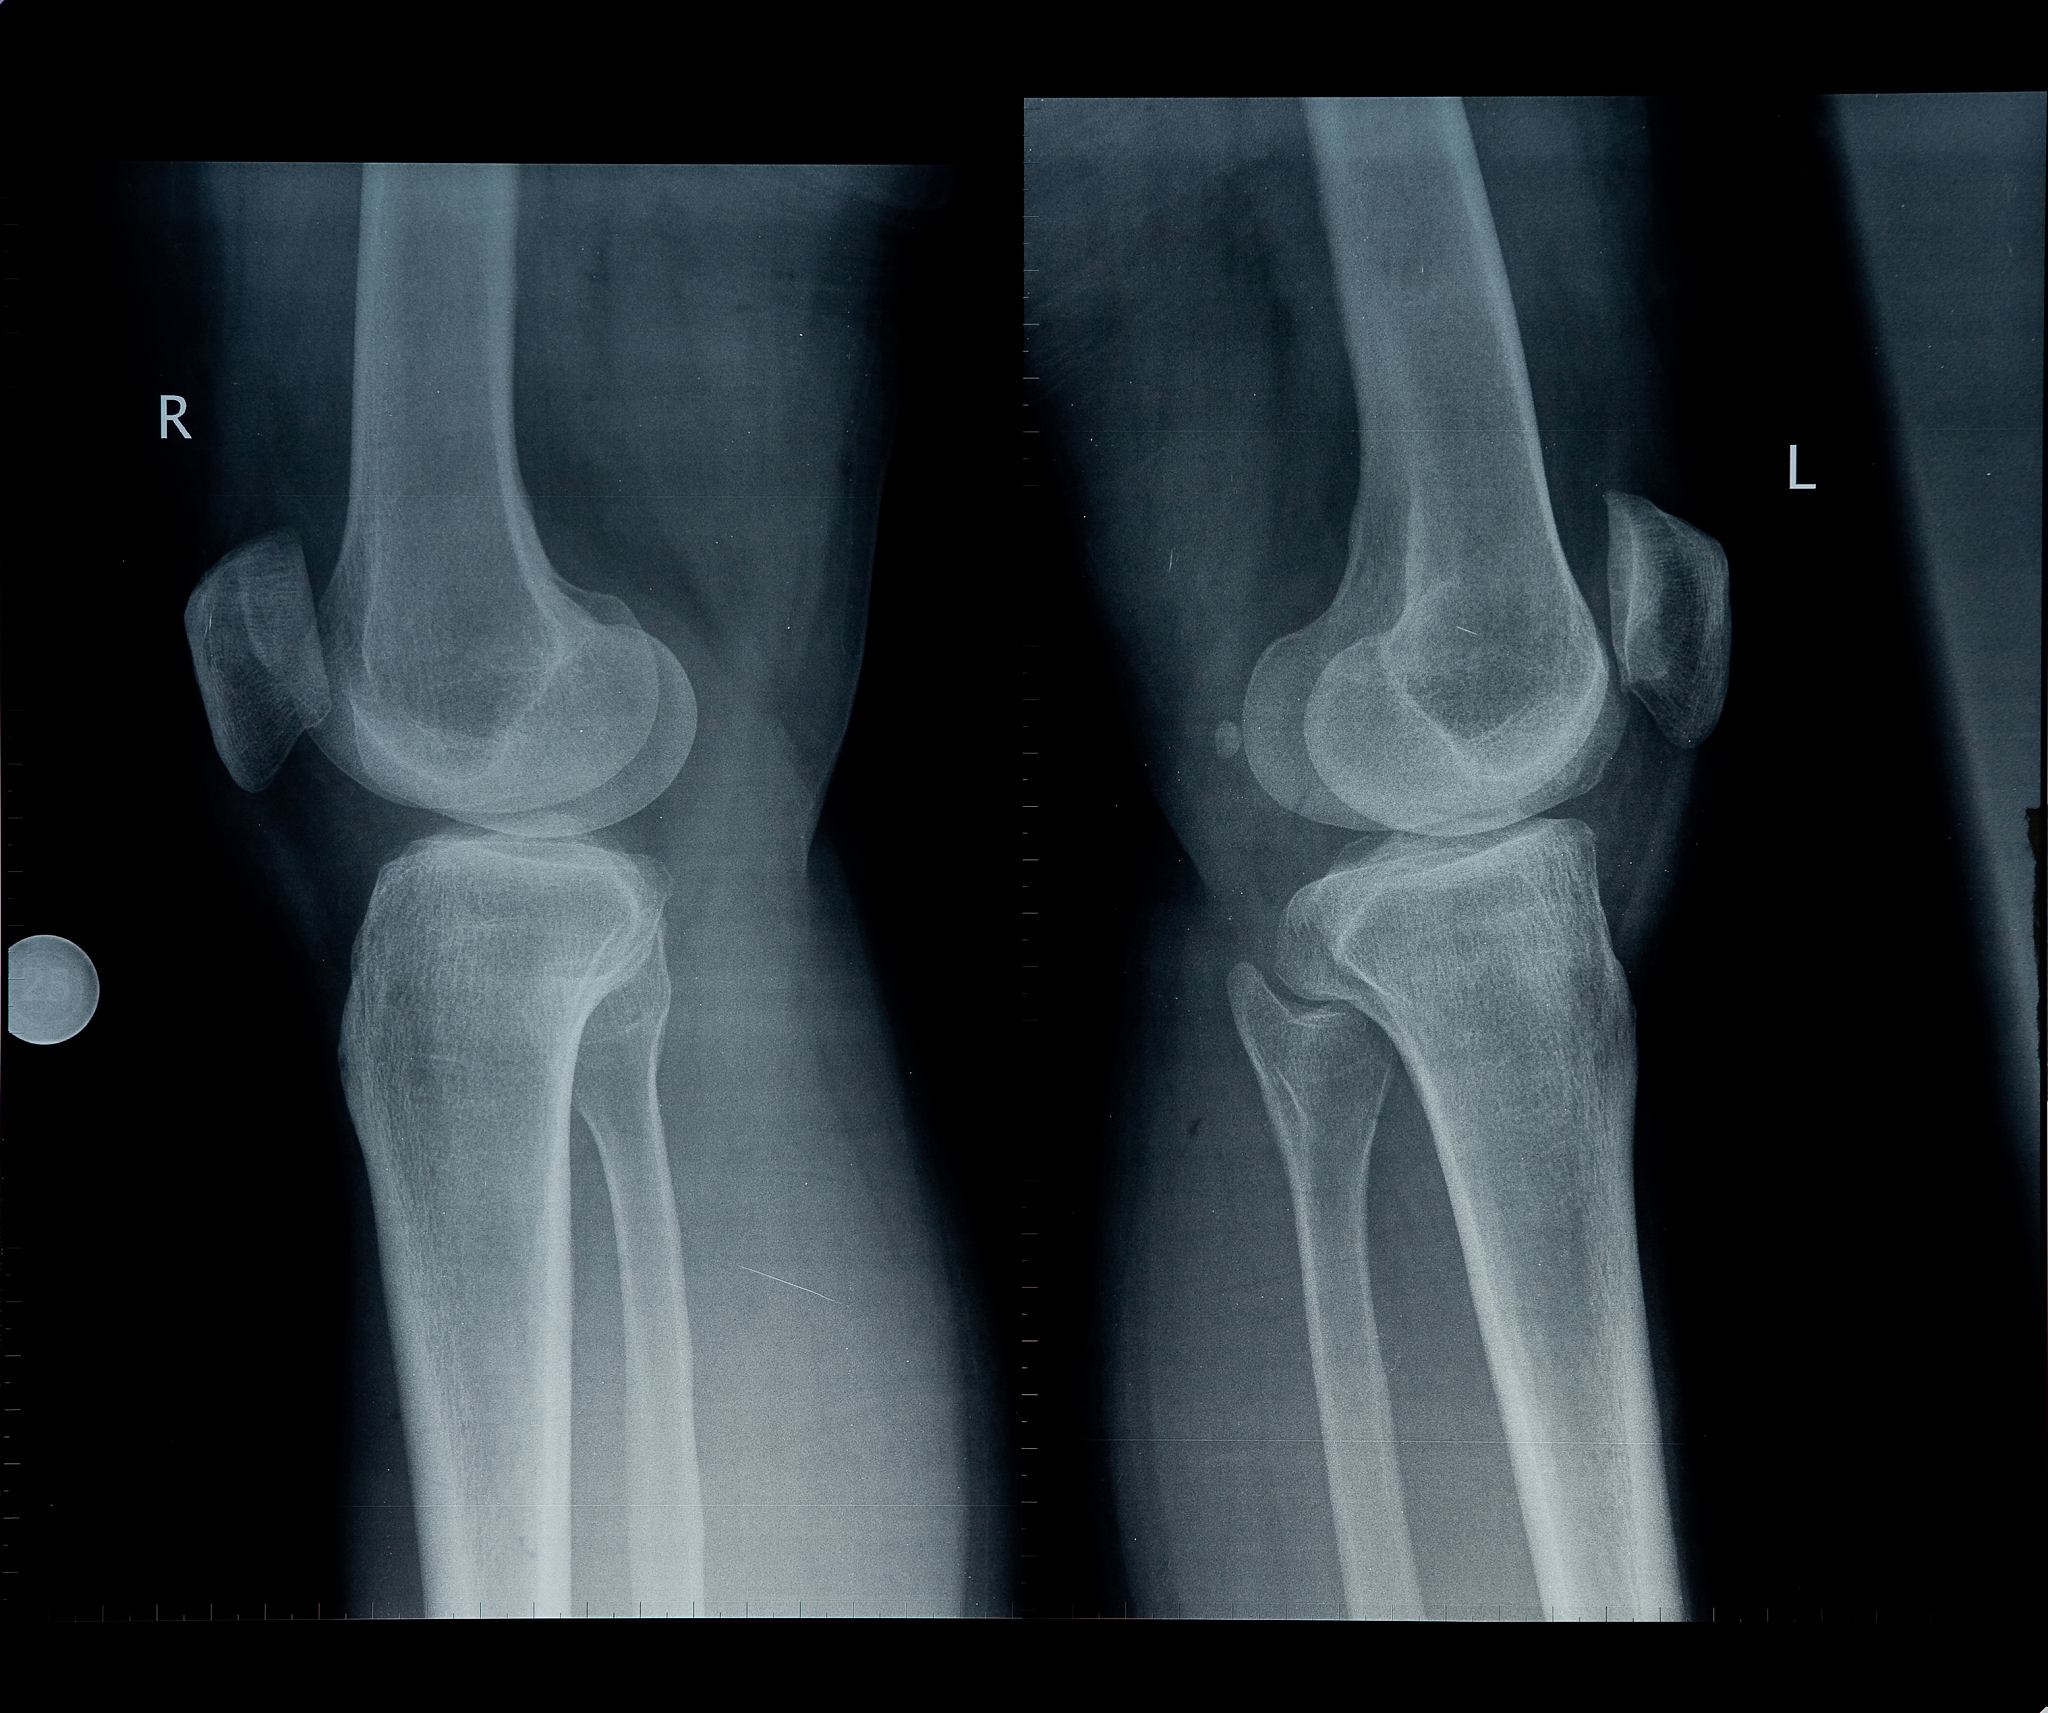

骨骺线是指儿童和青少年长骨骨干的两个骨端之间的软骨区域。这些软骨区域在骨骼发育过程中起着重要作用,直到骨骼发育成熟。骨骺线最终会闭合,形成完全的骨质。闭合时间会因个体差异和不同骨骼部位而有所不同。

通常情况下,女性的骨骺线闭合比男性早。一般来说,躯干骨骺线在18-25岁之间闭合,上肢骨骺线在16-19岁之间闭合,下肢骨骺线在18-23岁之间闭合。然而,请注意这只是一个大致的参考范围,个体之间仍然存在差异。影响骨骺线闭合的因素包括遗传、生长激素、性别、营养状况和整体健康状况等。

对于一个具体个体的骨骺线闭合情况,最好咨询专业医生或骨科专家,他们可以通过临床检查和骨龄评估来判断。